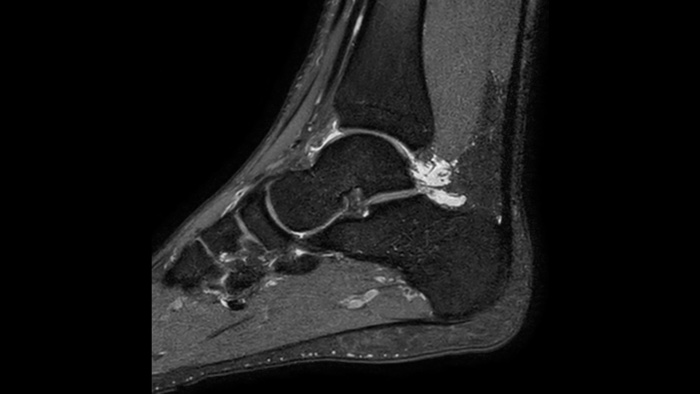

確信が持てる画像診断 同じスキャン時間で、空間分解能を最大65%向上⁴

確信が持てる画像診断 すべての臨床領域でイメージング機能を拡張します。医療従事者が享受できるメリットをご覧ください。

1 稀なケースとして、マグネットの密封が損なわれた場合でもヘリウムの量はわずかであるため、漏れたヘリウムが室内の酸素レベルに影響を与えることは実質的にありません。 2 Philips SENSEとの比較。 3 心拍数が低い (50 bpm) とき。Compressed SENSEなしのフィリップススキャンと比較した場合。 4 等方性3D MSK VIEWスキャンで、Compressed SENSEなしのフィリップススキャンと比較した場合。